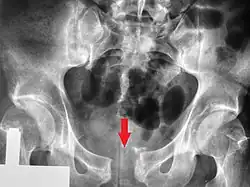

| A pelvic X-ray showing an open book fracture | |

A pelvic fracture is a break of the bony structure of the pelvis.[1] This includes any break of the sacrum, hip bones (ischium, pubis, ilium), or tailbone.[1] Symptoms include pain, particularly with movement.[1] Complications may include internal bleeding, injury to the bladder, or vaginal trauma.[2][3]

Common causes include falls, motor vehicle collisions, a vehicle hitting a pedestrian, or a direct crush injury.[2] In younger people significant trauma is typically required while in older people less significant trauma can result in a fracture.[1] They are divided into two types: stable and unstable.[1] Unstable fractures are further divided into anterior posterior compression, lateral compression, vertical shear, and combined mechanism fractures.[2][1] Diagnosis is suspected based on symptoms and examination with confirmation by X-rays or CT scan.[1] If a person is fully awake and has no pain of the pelvis medical imaging is not needed.[2]